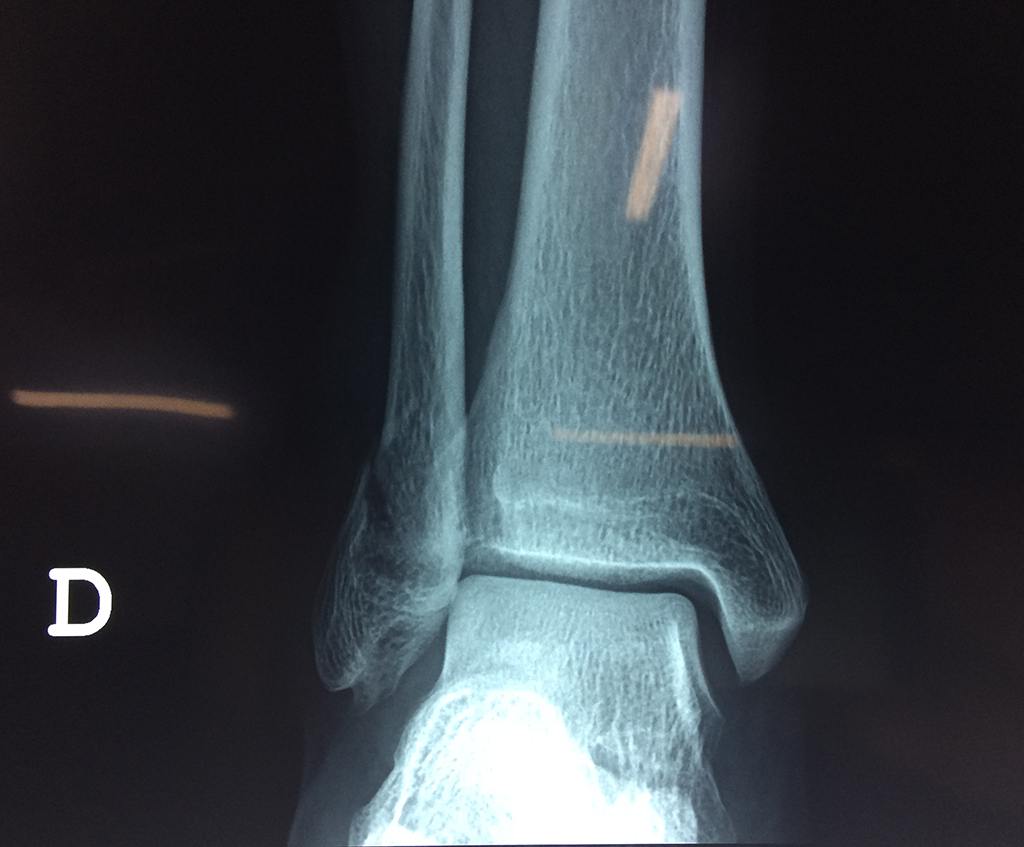

Cirugías de Peroné y Tibia

Una fractura de tobillo es la rotura de uno o más de los huesos del tobillo. Estas fracturas pueden ser:

Algunas fracturas de tobillo pueden requerir cirugía si:

Cuando se necesita cirugía, es probable que esta implique el uso de clavijas de metal, tornillos o placas para sostener los huesos en su lugar mientras la fractura se consolida. Los elementos de soporte pueden ser temporales o permanentes.